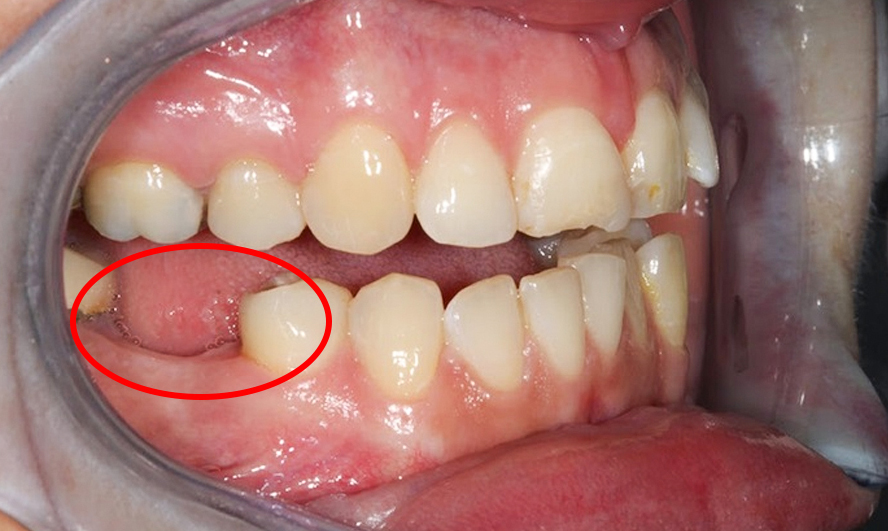

- Viêm nha chu: Tình trạng viêm nướu khiến nướu bị tụt xuống và chân răng bị hở dẫn đến tiêu hủy xương và dây chằng bao bọc răng, khiến răng mất đi sự nâng đỡ, lung lay, rụng dần.

- Về sức khỏe: Hiện tượng tụt nướu là diễn biến tất yếu sau khi khối lượng xương hàm bị tiêu giảm đáng kể. Đặc biệt khi vi khuẩn xâm nhập vào răng và xương hàm có thể gây đau nhức và dẫn đến nhiều bệnh lý khác.

- Về ăn nhai: Phần xương hàm bị hóp do giảm thể tích sẽ có xu hướng trả lại các răng kế cận cho các răng đã mất. Điều này có thể khiến răng bị lung lay và dễ gãy. Việc ăn nhai cũng bị suy giảm đáng kể.

- Chức năng thẩm mỹ: sau khi bị mất thẩm mỹ, cấu trúc hàm dưới mất cân đối, má hóp, da nhăn nheo, lão hóa sớm. Những người bị tiêu xương thường già sớm, thậm chí khuôn mặt còn bị biến dạng.